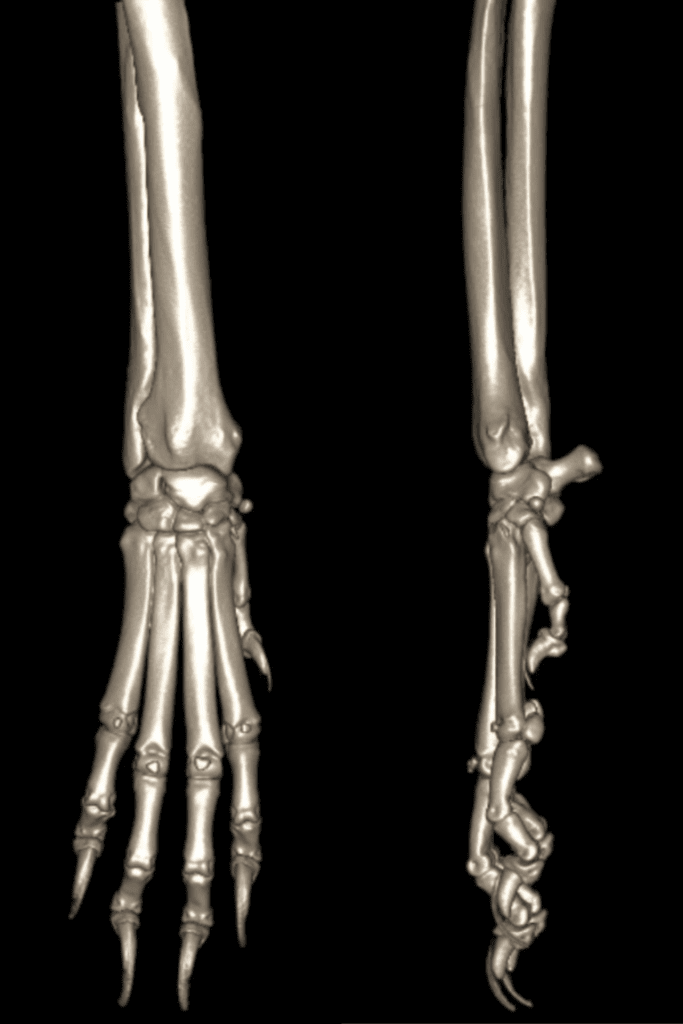

Nico’s CT scan for his carpal (wrist) laxity

Nico the wonderful wolfhound was struggling to weight bear on his right carpus and his neurologist mum Nadia Shihab brought him to see our orthopaedic team.

A physical examination showed carpal laxity on the right carpus so his orthopaedic surgeon immediately referred Nico for a CT scan using our 160-slice CT scanner to help him work out exactly what was happening in that joint. The high-resolution CT images were obtained in seconds, offering superior resolution of the bony anatomy, identifying small and subtle pathology and allowing 3D reconstruction of Nico’s carpus.

The diagnosis was progressive carpal collapse and treatment options included a pan carpal arthrodesis using a custom implant designed and modelled from the CT images so that it could fit Nico’s bones perfectly.